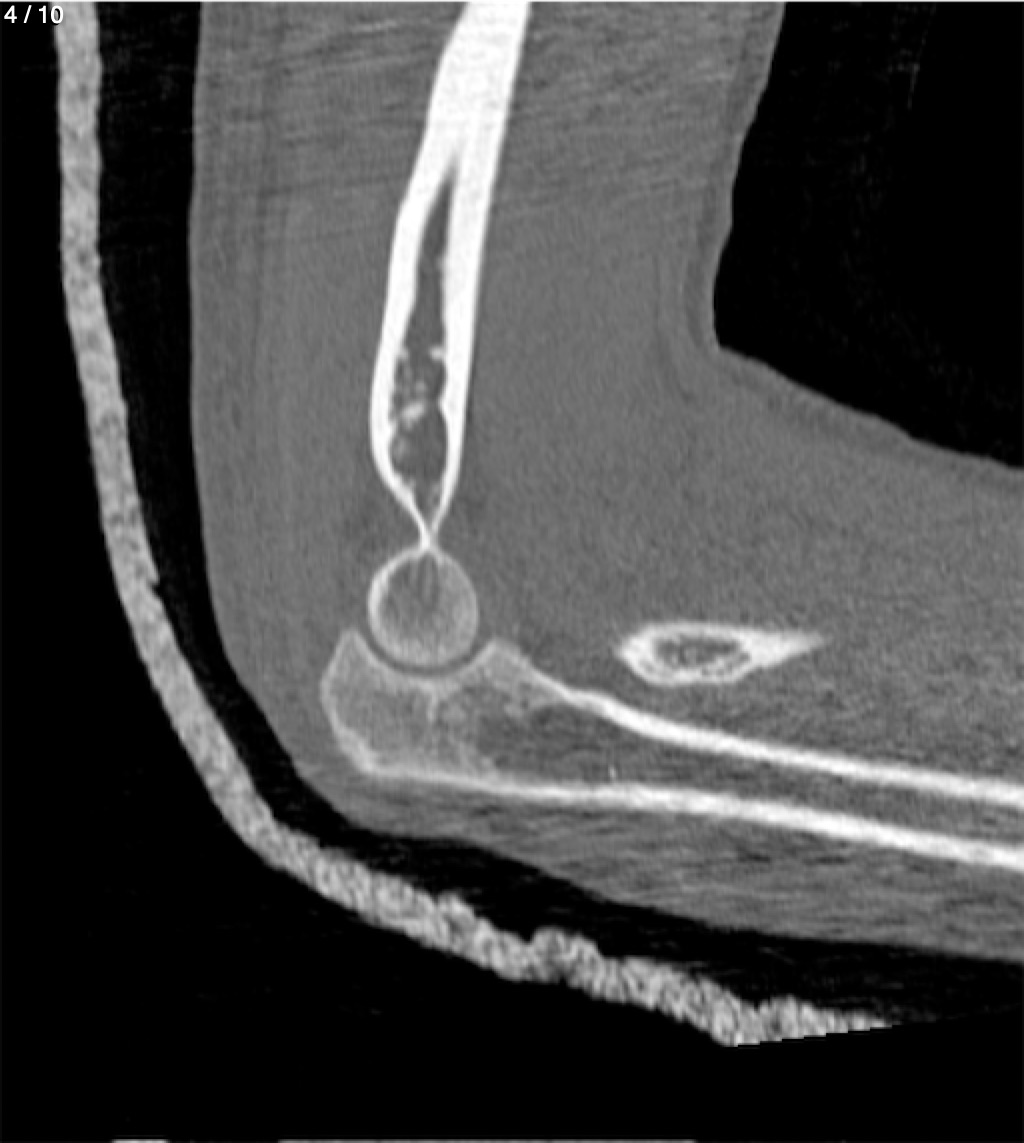

Antonio Dominguez Tino 21 A - Tac Codo Izq